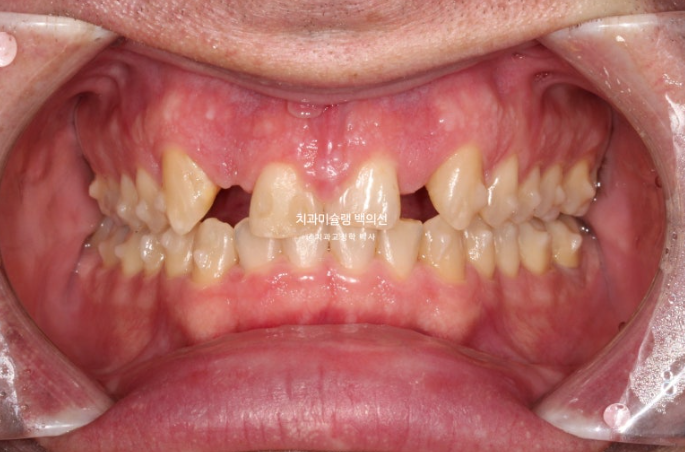

24년 4월까지 5개월간 24개 추가장치를 모두 낀 후 모습입니다.

24.04

중심선은 잘 맞으며 쓰러진 앞니 뿌리 및 중절치 단차는 개선되었습니다.

어금니 교합도 양측 모두 1급 달성되었고 뜨는 부분도 없습니다.

임플란트 식립 부위를 좀 더 안정적으로 만들기 위해서 두번째 추가장치 제작에 들어갑니다.

보이는 부분은 아니지만 환자분을 위해 필요한 치료입니다.

24년 5월부터 10월까지 20개 장치를 더 낀 후 교정치료를 종료했습니다.

24.10